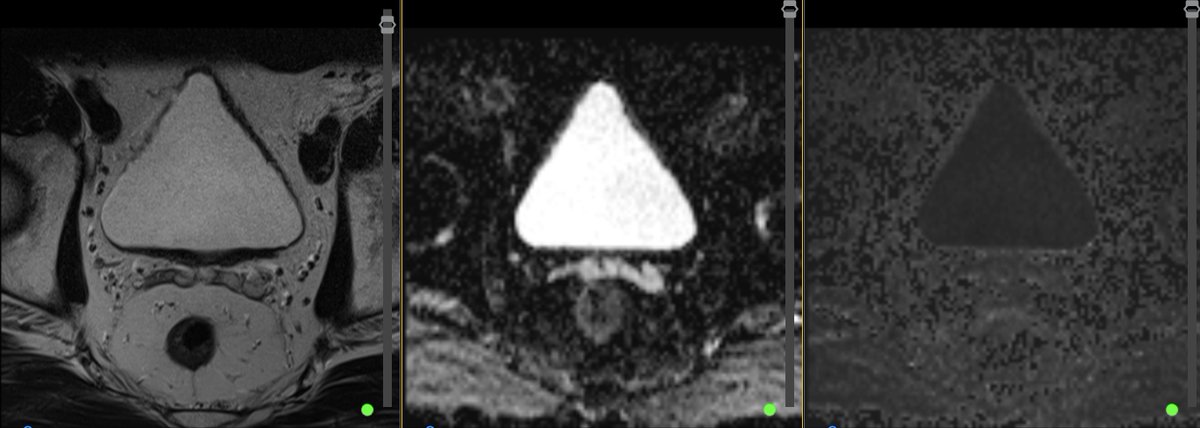

What do we make of the results of the randomised trial of transrectal vs transperineal prostate biopsy?? GU Cast Renu Eapen Declan Murphy discuss the PREVENT trial with PI Jim Hu and jeremy grummet youtu.be/eVoDI6vIKcs?si…